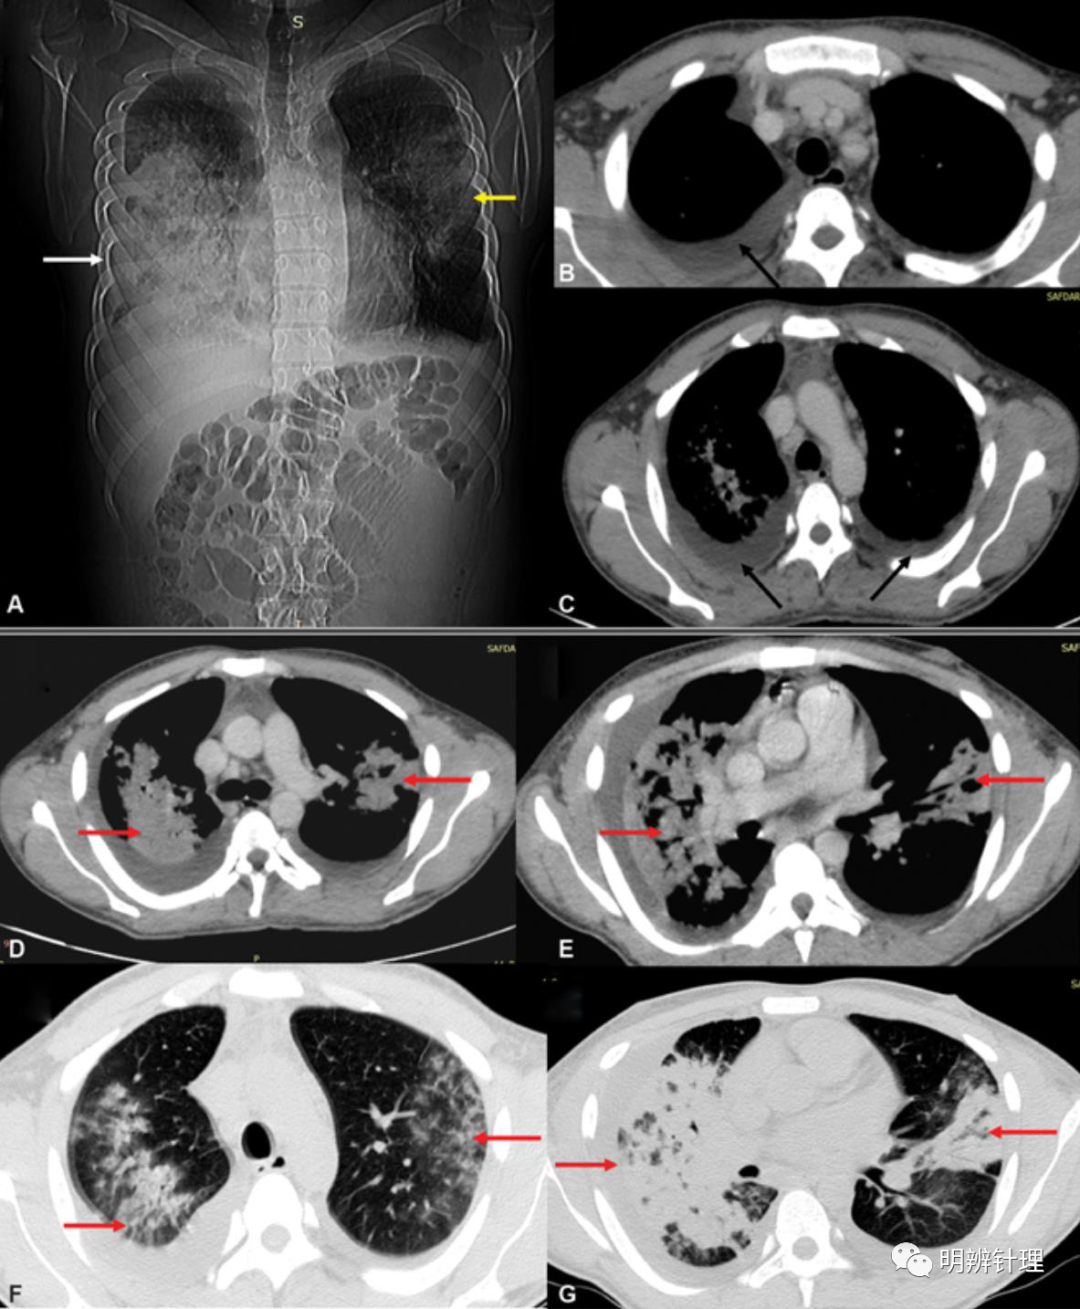

男性,22 岁,出现高烧、咳嗽,有长期酗酒。( A ) 显示右肺下叶实变(白色箭头)伴有隆起的水平裂隙和左肺浸润(黄色箭头)。对比增强CT显示双侧胸腔积液(黑色箭头)、气管旁淋巴结肿大( B、C )。肺窗 ( D–G ) 显示广泛的双侧斑片状实变,伴有空气支气管征(红色箭头)。

诊断结果: 血培养:假单胞菌和葡萄球菌